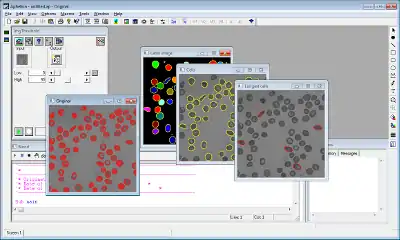

The main principle of image processing is to automatically process pixels of a digital image, then extract one or more objects of interest (i.e. cells in the field of biology, inclusions in the field of material science) and compute one or more measurements on those objects to quantify the image and generate a verdict (good image, image with defects, cancerous cells). In other words, starting from an image, pixels are processed by a set of successive functions or operators until only measurements are computed and used as the input of a 3rd party system or a classification software that will classify objects of interest that have been extracted during the imaging process.

The goal of image processing is usually to extract object(s) of interest in an image, and then to classify them based on some characteristics such as shape, density, position, etc. Using Aphelion, this goal is achieved by performing the following tasks:

- Load an image from disk or acquire an image using an acquisition device.

- Enhance the image removing noise or modifying its contrast.

- Segment the image extracting objects of interest to be measured and analyzed. Typically, for simple applications, a threshold is performed to generate a binary image. Then, morphological operators are applied to clean the image and only keep objects of interest. Finally, a label value is given to each object based on its connectivity (4 or 8 connectivity when a square grid is used), and the background of the image is given value zero.

- The set of objects can be manually edited by the user to remove artifacts, and alter their edges. Objects can then be measured in terms of shape, color, densitometry, and then classified using the measurements.

In the field of cytopathology, ADCIS developed a set of software products such as a specific software to analyze blood composition, count and classify red globules,[6] and another software to automatically classify cancerous cells using a classification based on multiple neural networks.[51][52] Images are first acquired by a video camera mounted on an automated optical microscope. They are then automatically processed by Aphelion, and cytoplasm and nuclei are segmented using a watershed algorithm. Aphelion has also been used to study tumor vascularization in low resolution images using a slide scanner (much cheaper than a scan microscope).[53] The software that was developed helped the detection of immune-marked cells.[28] Image analysis is also used in histology to study angiogenesis in 2D and 3D on microscopy images[54] to measure effects of inhibitors and accelerants impact on blood vessels growth.